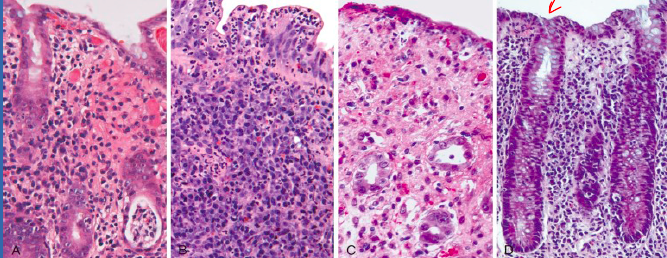

Eosinophilic Esophagitis

can present by itself or be part of eosinophilic gastroenteeritis

idiopathic EoE is common, seen frequently in children w atopic symptoms

This buildup, which is a reaction to foods, allergens or acid reflux, can inflame or injure the esophageal tissue. Damaged esophageal tissue can lead to difficulty swallowing or cause food to get caught when you swallow.

Eosinophilic esophagitis is a chronic immune system disease. It has been identified only in the past two decades, but is now considered a major cause of digestive system (gastrointestinal) illness.